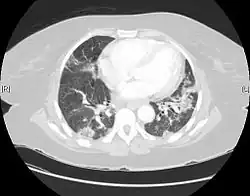

CT scan of a patient with UIP. There is interstitial thickening, architectural distortion, honeycombing and bronchiectasis. | |

UIP may be diagnosed by a radiologist using computed tomography (CT) scan of the chest, or by a pathologist using tissue obtained by a lung biopsy.

Radiology

Radiologically, the main feature required for a confident diagnosis of UIP is honeycomb change in the periphery and the lower portions (bases) of the lungs.[3]

On high-resolution computed tomography (HRCT), the following categories, depending on imaging findings, have been recommended by a collaborative effort by the American Thoracic Society, European Respiratory Society, Japanese Respiratory Society, and the Latin American Thoracic Society:[4]

- UIP pattern:[4]

- Honeycombing, with or without peripheral traction bronchiectasis; or bronchiolectasis (dilatation of the terminal bronchioles)[5]

- Predominantly subpleural and basal

- Often heterogenous distribution, being occasionally diffuse, and may be asymmetrical

There may be superimposed CT features such as mild ground-glass opacity, reticular pattern and pulmonary ossification.